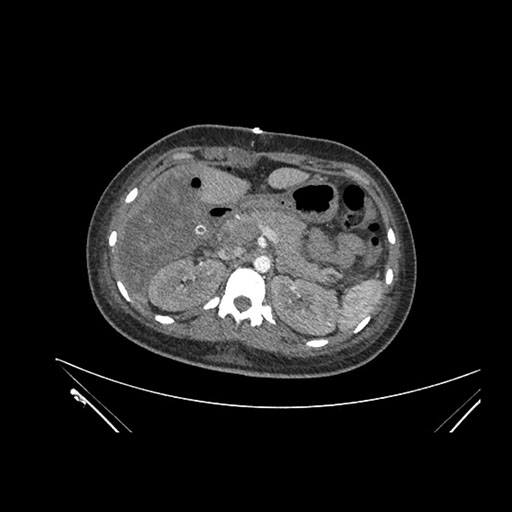

Axial Venous

Imaging analysis

Based on initial findings, which issue(s) would you be most concerned about?